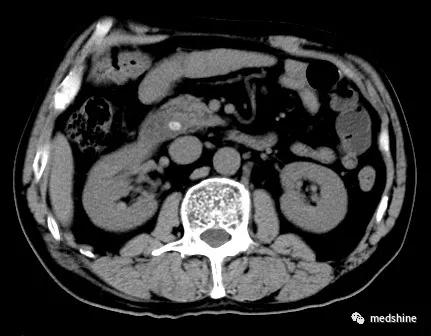

部分胆囊结石患者合并胆总结石,如果术前或术中没有发现胆管结石单纯实施了胆囊切除手术,就会导致胆总管残余结石,术后可能会出现相应的问题。还有少数患者在胆囊切除多年以后新发胆总管结石。

胆总管结石

针对胆总管结石,如果大于3.5mm,不论有无症状,一旦发现都应进行治疗。目前主要有内镜下oddi括约肌切开取石和腹腔镜联合胆道镜手术取石两种方法,应根据具体情况合理选择 。